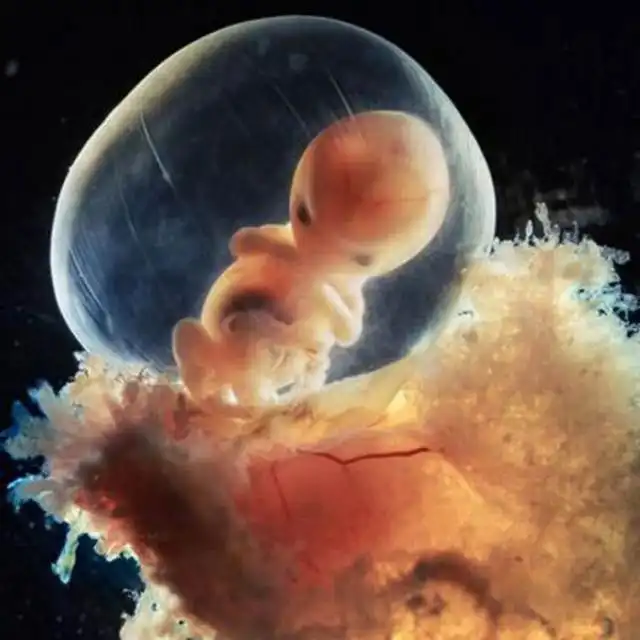

Через неделю зародыш, скользя вниз по фаллопиевой трубе, переселяется в матку...

Эмбрион, прикрепленный к слизистой матки (+8 дней)